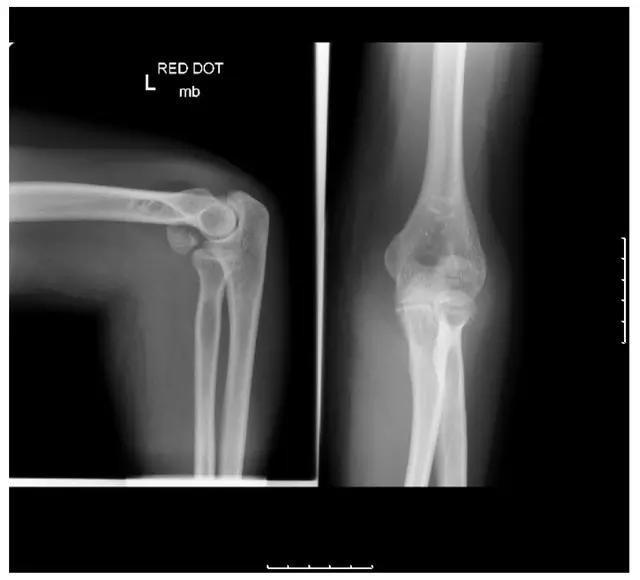

4. Holstein-Lewis 骨折

指肱骨远端 1/3 骨折伴桡神经嵌压。

Holstein-Lewis 骨折(来源:Humerus Holstein Lewis Fracture - Everything You Need To Know - Dr. Nabil Ebraheim)